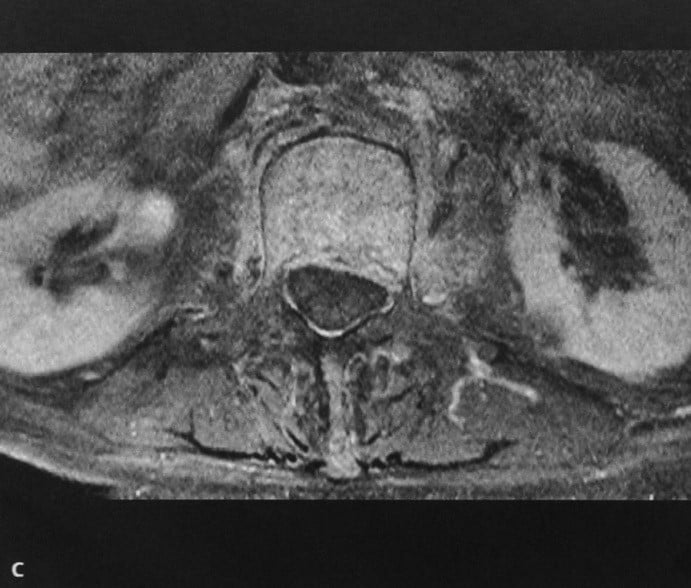

КТ диагностика тубоовариального абсцесса: Подходы и изображения

Раздел: Объективный взгляд